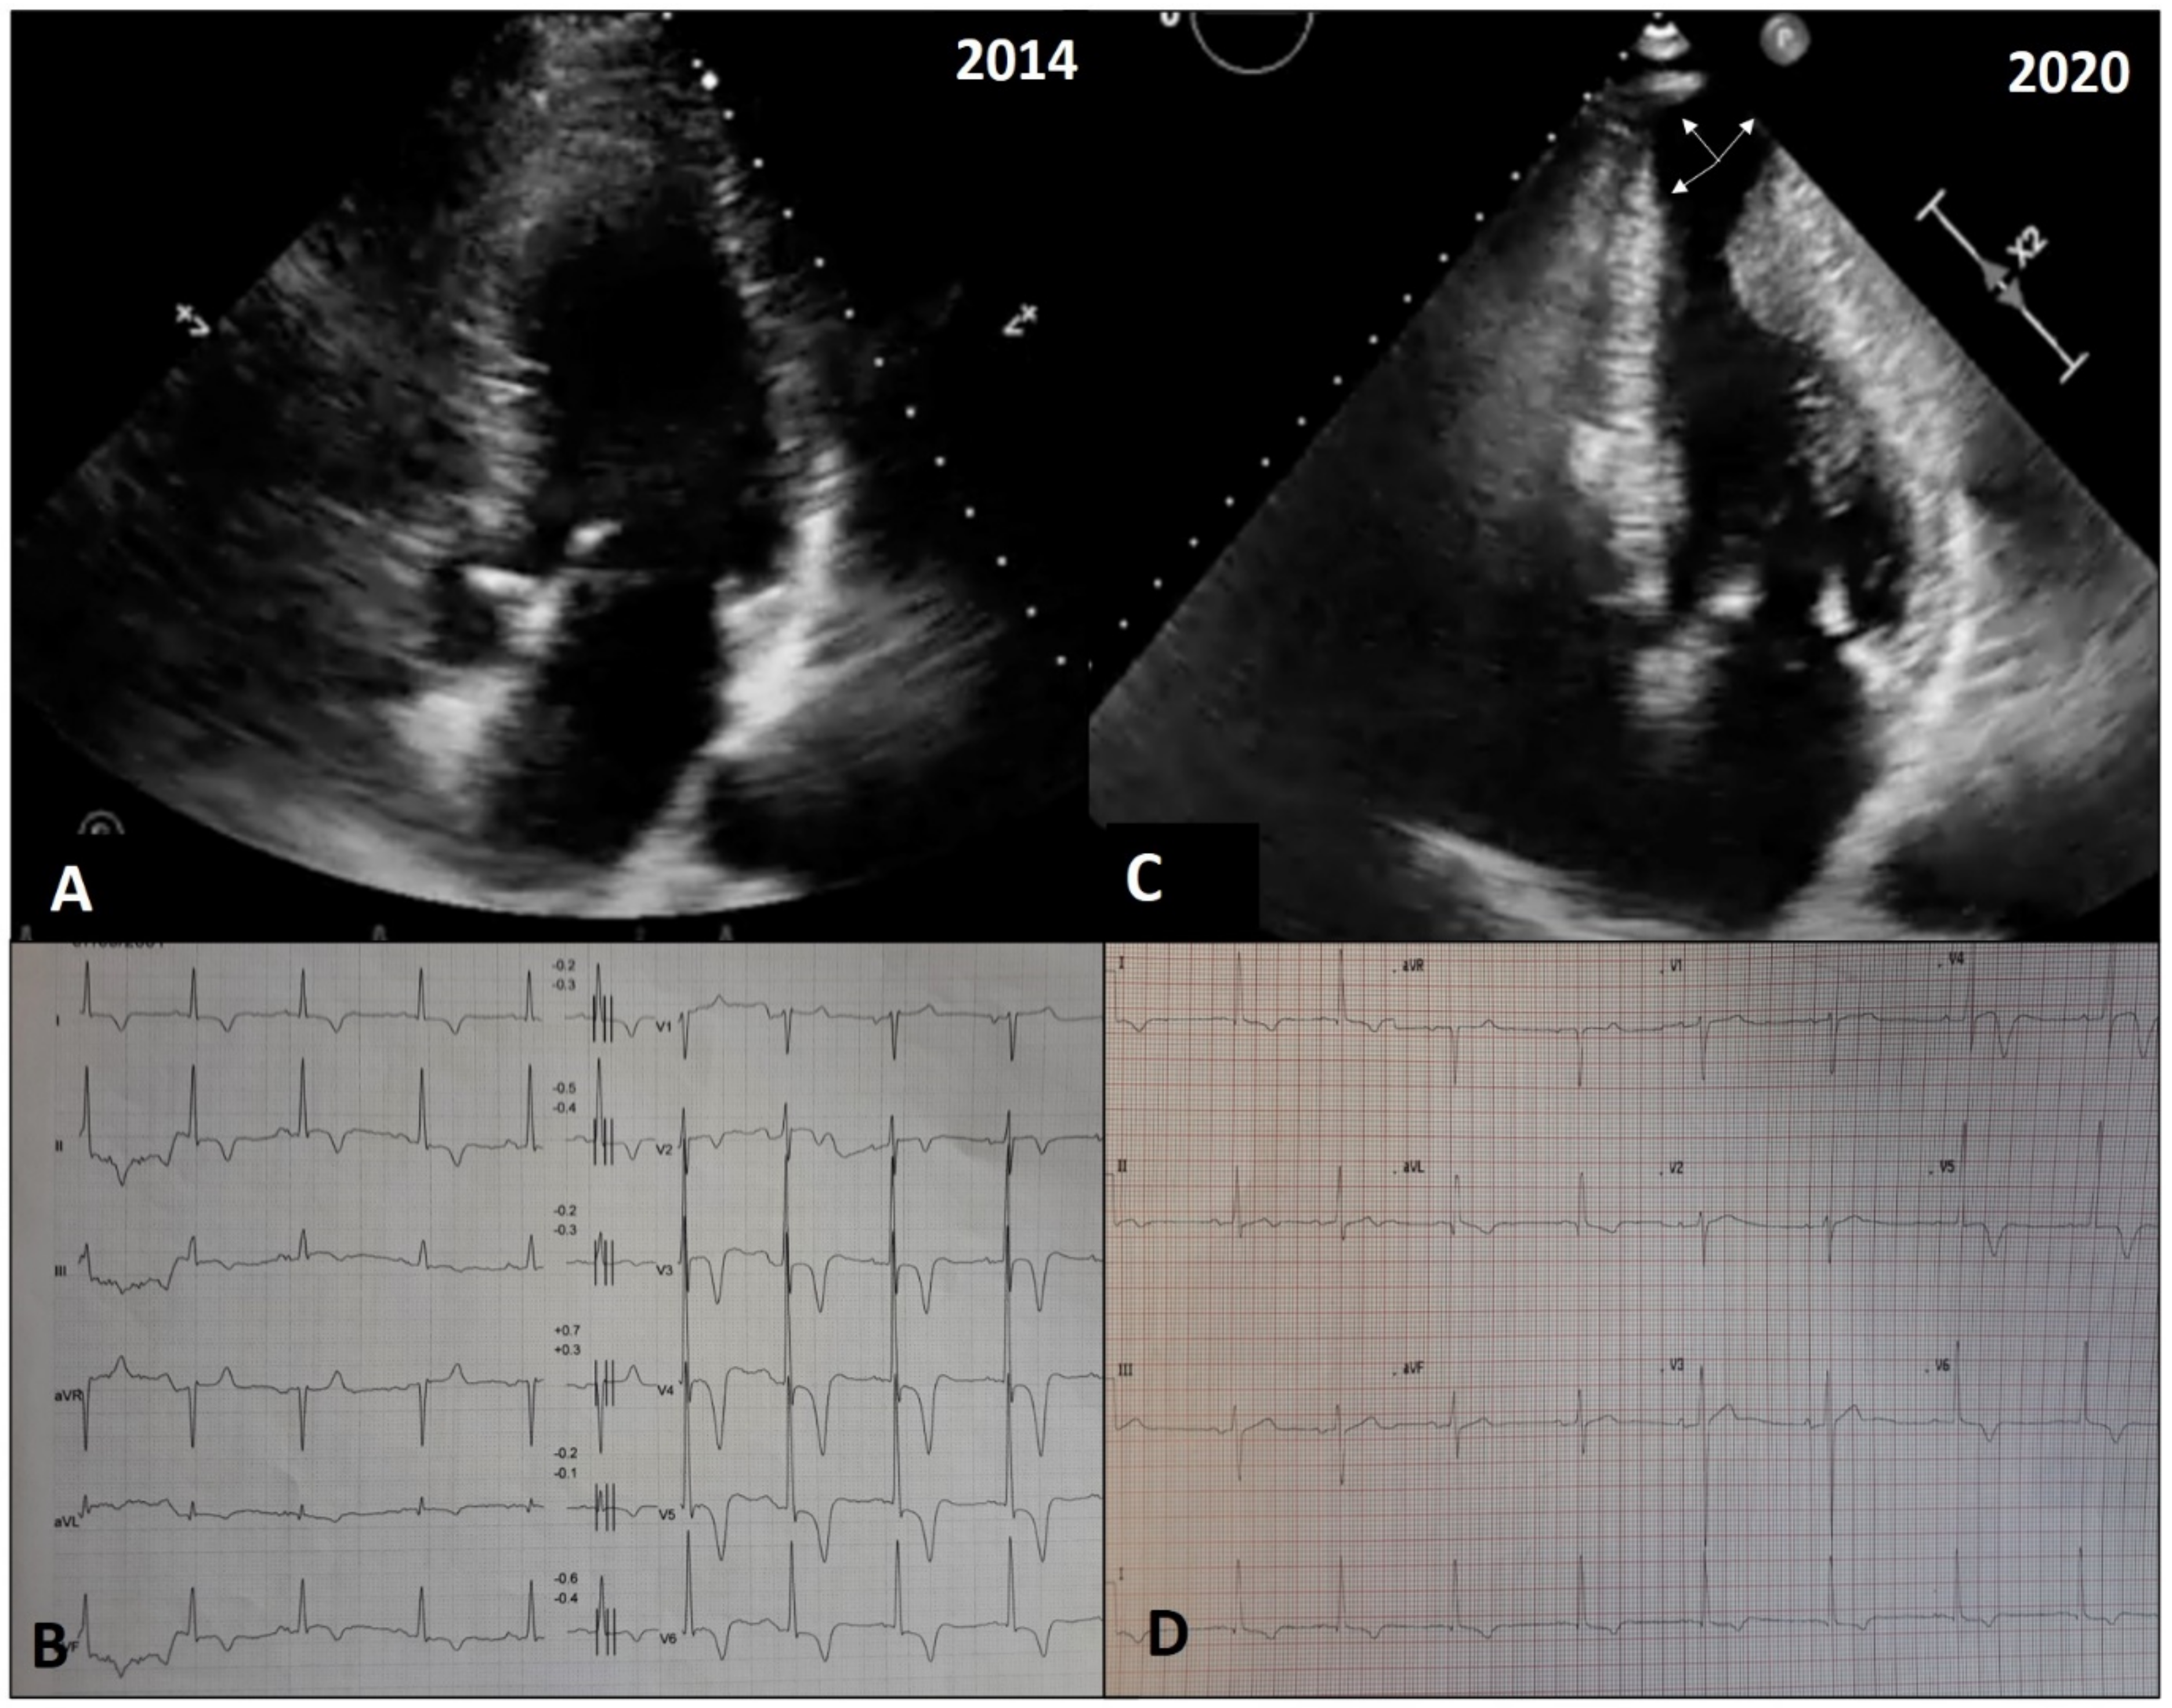

- Pennacchini, E.; Musumeci, M.B.; Conte, M.R.; Stöllberger, C.; Formisano, F.; Bongioanni, S.; Francia, P.; Volpe, M.; Autore, C. Electrocardiographic evolution in patients with hypertrophic cardiomyopathy who develop a left ventricular apical aneurysm. J. Electrocardiol. 2015, 48, 818–825. [Google Scholar] [CrossRef] [PubMed]